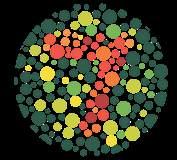

має форму двоввігнутого диска (мал. 9.3), що збільшує площу поверхні для газообміну порівняно з кулястою формою. Еритроцити гнучкі, тож можуть протискуватися вузькими капілярами. У людини, як і у всіх ссавців, еритроцити є без’ядерними. Еритроцити заповнені молекулами гемоглобіну білка, який містить гем із катіоном Fe2+, що

Аглютиногени системи

у таблиці 2.

Якщо, наприклад,

ві А (ІІ), то на

аглютиноген А, а в

нін β. Переливання їй донорської крові групи В (еритроцити містять аглютиноген В) призведе до злипання еритроцитів, оскільки аглютині-

ни β плазми реципієнта зв’язують аглютиноген В як чужорідний агент.

Таким чином, для успішного переливання донорська кров має містити такі самі аглютиногени, як і

еритроцитів білка, який називається резус-фактор. Якщо в людини еритроцити мають резус-фактор, то вона резус-позитивна, якщо не мають резус-негативна. Резус-фактор також обов’язково враховується під час переливання крові, бо імунна система резус-негативних людей реагує на резус-позитивну кров як на чужорідну. Запитання